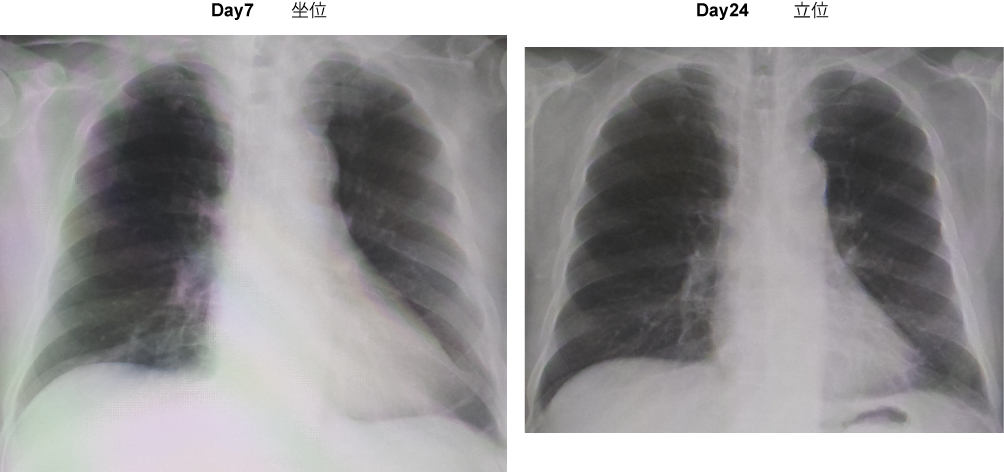

・胸部Xp

Day5:胸部CTで両側下肺野浸潤影。CRP 7.15。ユナシン-S開始。

Day7:喀痰培養でMRSA、ヘモフィルス同定。貪食像(+)。CRP 9.15。ユナシン-S中止。ゾシン、バンコマイシン開始。

Day20:抗生物質中止。CRP 0.13